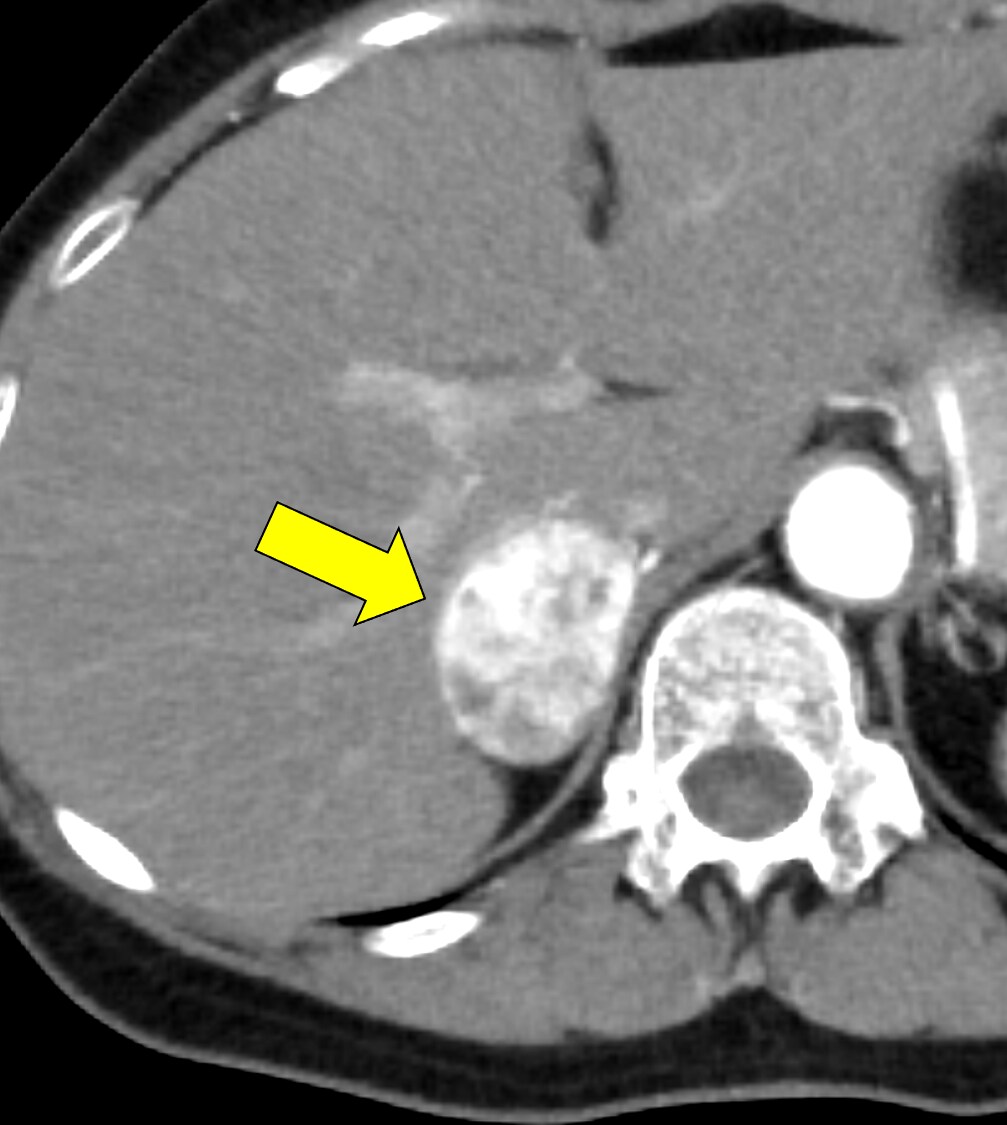

本例は、偶発的に指摘された右副腎腫瘍である。高血圧はあるが内服せず経過観察されている患者で、1cm/5年程度の非常に緩徐な増大を示す多血性の腫瘍を認める。腫瘍はI-123MIBGシンチ陰性であり、内分泌内科での精査においてもホルモン産生を疑う所見に乏しく、褐色細胞腫よりも海綿状血管腫が疑われていた。しかし、増大傾向があり破裂や出血のリスクなども考慮されて手術の方針となった。手術中に血圧の変動を認め、病理で褐色細胞腫の診断となった。

褐色細胞腫は副腎髄質に存在するクロム親和性細胞に由来する腫瘍で、カテコールアミンなど種々の生理活性物質を産生する。ダイナミック造影で動脈相での強い濃染と持続する造影効果が特徴とされ、サイズが大きい病変は嚢胞変性や出血、壊死を伴うことが多い。かつては、臨床的に褐色細胞腫が疑われる場合、ヨード造影剤の投与はカテコールアミンの過剰放出を誘発し、高血圧クリーゼを引き起こす可能性があるため原則禁忌とされていた。しかし、現在汎用されている非イオン性・低浸透圧性造影剤であればこの現象は起こらないとの報告もあり、European Society of Urogenital Radiology Guidelines on Contrast Media, ver 10.0では、「経静脈的ヨード造影剤の投与をする場合でも特別な準備の必要はない」と記載されている。イオプロミドの電子添文上は、禁忌にはなっていないものの、「慎重に投与すること」との記載になっている。本例では、血管腫疑いとして合計5回の造影CTが行われているが、血圧変動や頭痛、動悸などの症状は一度も認められなかった。

本例の画像所見として、褐色細胞腫としてダイナミック造影の濃染パターンは典型的ともいえたが、大きさの割に変性が乏しい点、MIBGシンチでの核種集積に乏しい点、ホルモン産生に乏しい点など非典型的な要素が複数存在し、海綿状血管腫を除外しきれなかった。なお、褐色細胞腫はRET遺伝子変異による多発性内分泌腺腫症(multiple endocrine neoplasia;MEN)type 2A・2B、VHL遺伝子によるvon Hippel-Lindau病、NF1遺伝子による神経線維腫症1型に生じることが知られているが、これらの疾患を想起させるような他病変は本例には見つかっていない。

CT技術や撮像プロトコル設定について

腺腫や骨髄脂肪腫など良性と断定できない副腎腫瘍の鑑別をする際、大きい病変であれば褐色細胞腫や副腎癌、悪性リンパ腫などが考慮される。核医学検査も有用ではあるが、本例のように偽陰性となることも稀にあり、その際はダイナミック造影パターン、血管への浸潤、転移の有無などから判断しなければならない。適切なタイミングで撮像されたダイナミック造影CTは、多血性病変であるかの評価、周囲の血管との関係性、多血性の転移巣の有無などの判断に寄与し、診断の重要な手がかりとなると考える。